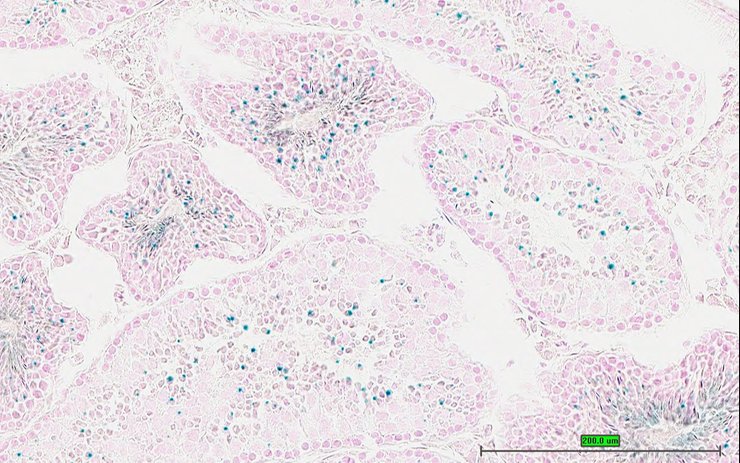

TS28: testis Present UC Davis_1880896

Specimen UC Davis_1880897: postnatal adult; Ifi204tm1b(KOMP)Wtsi/Ifi204+ (more )

Structure Level Pattern Image Note

TS28: testis Present UC Davis_1880897